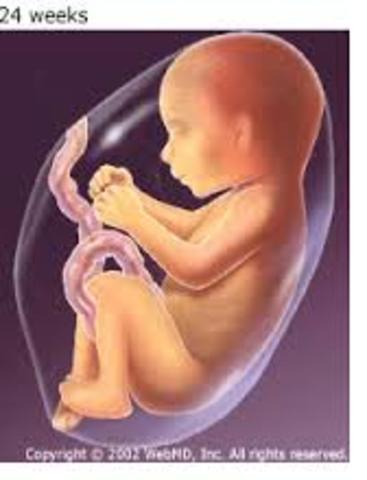

• 6th Month

6th Month

1. Eyes are fully developed.

2. The baby can hear.

3. Taste buds form.